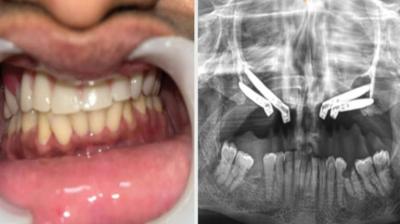

एम्स भोपाल में जटिल सर्जरी सफल, युवती को मिला नया जीवन

6 Sep, 2025 10:00 PM IST | BHUANAKIMATI.COM

एम्म में जटिल सर्जरी को सफलतापूर्वक अंजाम दिया है। इस सर्जरी में ट्यूमर के कारण काटे गए निचले जबड़े को पैर की हड्डी से दोबारा बनाया गया और उसमें 13...